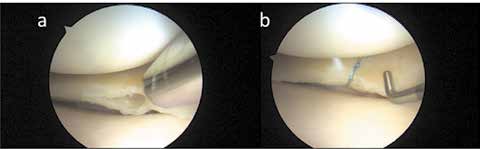

Der Verlust des Meniskus durch Verletzung oder Degeneration hat eine progrediente Gonarthrose zur Folge 13. Die Teilresektion symptomatischer Meniskusrisse degenerativer Genese weist überwiegend exzellente bis gute Resultate im mittleren Zeitverlauf auf. Die Teilresektion reduziert in systematischen Literaturanalysen langfristig die Symptome, wobei es dennoch nach 8 bis 16 Jahren zu radiologischen Zeichen einer Arthrose kommt. Je mehr Meniskusgewebe entfernt werden muss, umso höher ist das Risiko für die Entstehung einer Gonarthrose. Der symptomatische degenerative Riss stellt daher auch im höheren Stadium der Arthrose eine korrekte Indikation zur Arthroskopie dar. Der Erhalt des Meniskusgewebes durch eine Naht zeigt bessere Ergebnisse als die Resektion. Der Erfolg einer Naht nimmt dennoch bei Degeneration ab. Degenerative horizontale Risse neigen zur Progredienz in Richtung Gelenkkapsel und können schmerzhafte Ganglien oder Zysten bilden. Sie entstehen durch eine zentrale Meniskuserweichung mit der Schwächung vertikaler Fasern, wodurch obere und untere Meniskus-Schichten sich gegeneinander verschieben. Um den instabilen Meniskus mit dem Horizontalriss nicht bis zur Kapsel resezieren zu müssen, wird heute auch bei dieser Riss-Form eine All-inside-Naht nach Anfrischen der Rissflächen durchgeführt (Abb. 3).